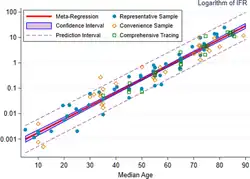

A key metric in gauging the severity of COVID‑19 is the infection fatality rate (IFR), also referred to as the infection fatality ratio or infection fatality risk.[353][354][355] This metric is calculated by dividing the total number of deaths from the disease by the total number of infected individuals; hence, in contrast to the CFR, the IFR incorporates asymptomatic and undiagnosed infections as well as reported cases.[356]

Estimates

A December 2020 systematic review and meta-analysis estimated that population IFR during the first wave of the pandemic was about 0.5% to 1% in many locations (including France, Netherlands, New Zealand, and Portugal), 1% to 2% in other locations (Australia, England, Lithuania, and Spain), and exceeded 2% in Italy.[357] That study also found that most of these differences in IFR reflected corresponding differences in the age composition of the population and age-specific infection rates; in particular, the metaregression estimate of IFR is very low for children and younger adults (e.g., 0.002% at age 10 and 0.01% at age 25) but increases progressively to 0.4% at age 55, 1.4% at age 65, 4.6% at age 75, and 15% at age 85.[357] These results were also highlighted in a December 2020 report issued by the WHO.[358]

An analysis of those IFR rates indicates that COVID‑19 is hazardous not only for the elderly but also for middle-aged adults, for whom the infection fatality rate of COVID-19 is two orders of magnitude greater than the annualised risk of a fatal automobile accident and far more dangerous than seasonal influenza.[357]

Earlier estimates of IFR

At an early stage of the pandemic, the World Health Organization reported estimates of IFR between 0.3% and 1%.[359][360] On 2 July, The WHO's chief scientist reported that the average IFR estimate presented at a two-day WHO expert forum was about 0.6%.[361][362] In August, the WHO found that studies incorporating data from broad serology testing in Europe showed IFR estimates converging at approximately 0.5–1%.[363] Firm lower limits of IFRs have been established in a number of locations such as New York City and Bergamo in Italy since the IFR cannot be less than the population fatality rate. (After sufficient time however, people can get reinfected).[364] As of 10 July, in New York City, with a population of 8.4 million, 23,377 individuals (18,758 confirmed and 4,619 probable) have died with COVID‑19 (0.3% of the population).[365] Antibody testing in New York City suggested an IFR of ≈0.9%,[366] and ≈1.4%.[367] In Bergamo province, 0.6% of the population has died.[368] In September 2020, the U.S. Centers for Disease Control and Prevention (CDC) reported preliminary estimates of age-specific IFRs for public health planning purposes.[369]